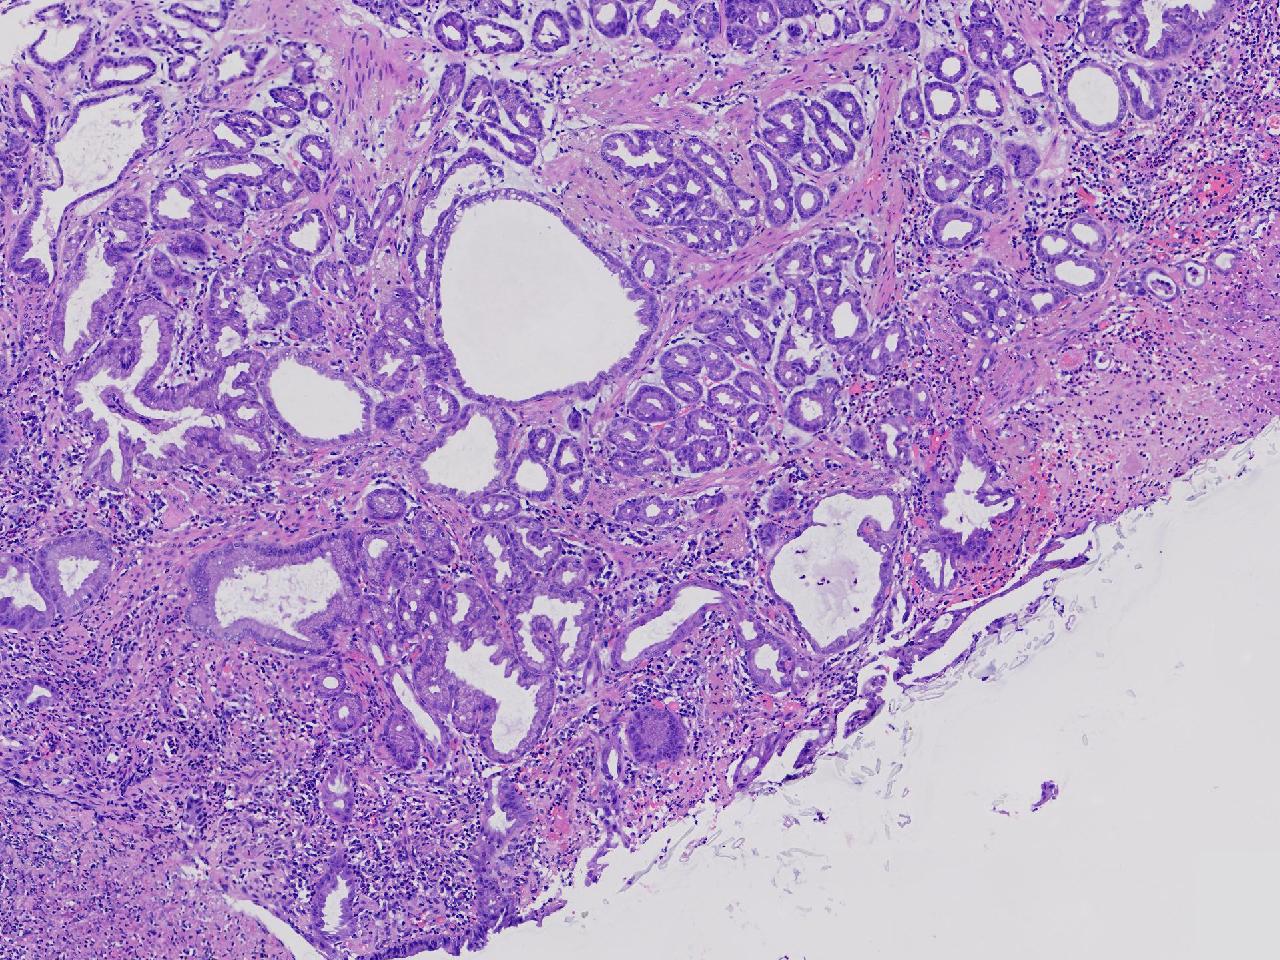

胃体上部见一大小约2厘米的溃疡灶,表覆白苔,周边充血,水肿明显,活检3块。

胃体活检

灰白色不整形软组织3块,直径均0.2厘米。

深在性囊性胃炎,少量溃疡组织

深在性囊性胃炎伴溃疡